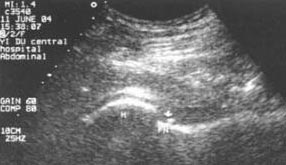

肌骨超声(musculoskeletal ultrasound,MSUS)技术是通过高频超声(3~17Hz)扫描提供优异的临床图像,以清晰显示肌肉等软组织层次关系及其内部机构来诊断肌肉骨骼系统疾病的新型超声检查技术。通过肌骨超声,医生可以分辨毫米级以下动态的这些组织结构肌肉、肌腱、韧带、关节囊、关节面及周围神经等浅表软的毗邻关系、形态大小、结构纹理、血流分布,从而获取这些组织器官的解剖变异、炎症、退行性病以及创伤等病变的全方位信息,从而对疾病进行精准评估。

动态观察滑膜血流信号,早期监测RA活动

清晰显示滑膜异常形态,定量评估RA炎性